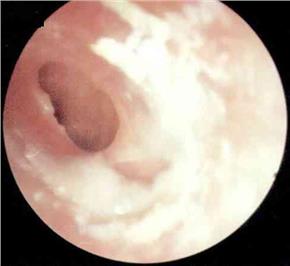

分泌性中耳炎病理图

医生表示:分泌性中耳炎不是由于细菌等微生物感染引起的耳部急性炎症,它以鼓室内积液引起听力减退为主要特征。在秋冬季节,它是比较常见的耳部疾病之一。是什么原因引起分泌性中耳炎的呢?耳病诊疗的张全安教授指出需从耳部的解剖结构说起。

耳朵通过咽鼓管与鼻咽部相通。咽鼓管可以调节耳内的压力,以此与大气压保持平衡,其外还有防御、清洁的功能。在秋冬季,日夜温差比较大,常会诱发上呼吸道感染,炎症波及咽鼓管时,耳内往往会形成负压,这时会产生耳闷的感觉。耳内的黏膜受负压影响分泌较多的液体,并由于咽鼓管功能障碍不能及时排出,积在耳内产生听力下降,耳朵里有水泡声,有时还会感到耳痛。